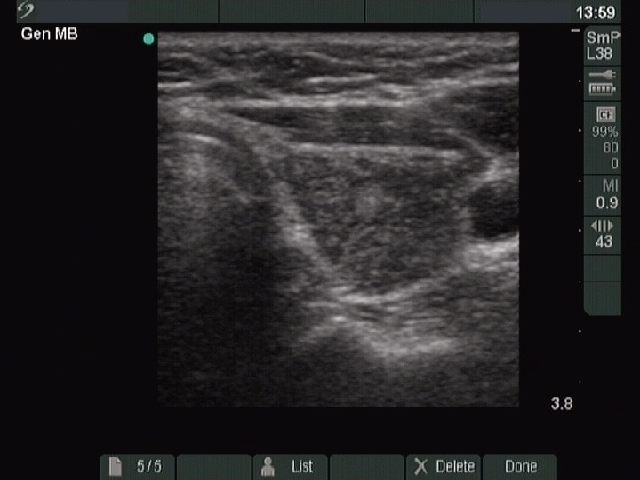

Ultrasonography. The two lobes differed in echo pattern. The right lobe (upper image) was echonormal and contained small hypoechogenic foci with an echogenicity index of less than 5% while the left lobe (lower images) was composed of a central hypoechogenic area surrounded with an echonormal rim, therefore it resembled a large hypoechogenic nodule comprising great proportion of the lobe . On the other hand the lesion had irregular borders and showed a heterogeneous pattern and similar smaller areas were found elsewhere in the lobe.

Cytological diagnosis: benign Hashimoto's thyroiditis.

Comment. The ultrasound pattern is remarkable, the left lobe highly resembles a pattern of a large hypoechogenic nodule. On thorough analysis of the images and the video, it seemed more likely that this area is not a nodule in a pathological sense but only more active focus of the underlying thyroiditis. The differentiation between a nodule in pathological sense and a hypoechogenic focus of Hashimoto's thyroiditis is not always possible, even in this case it not fully unequivocal.